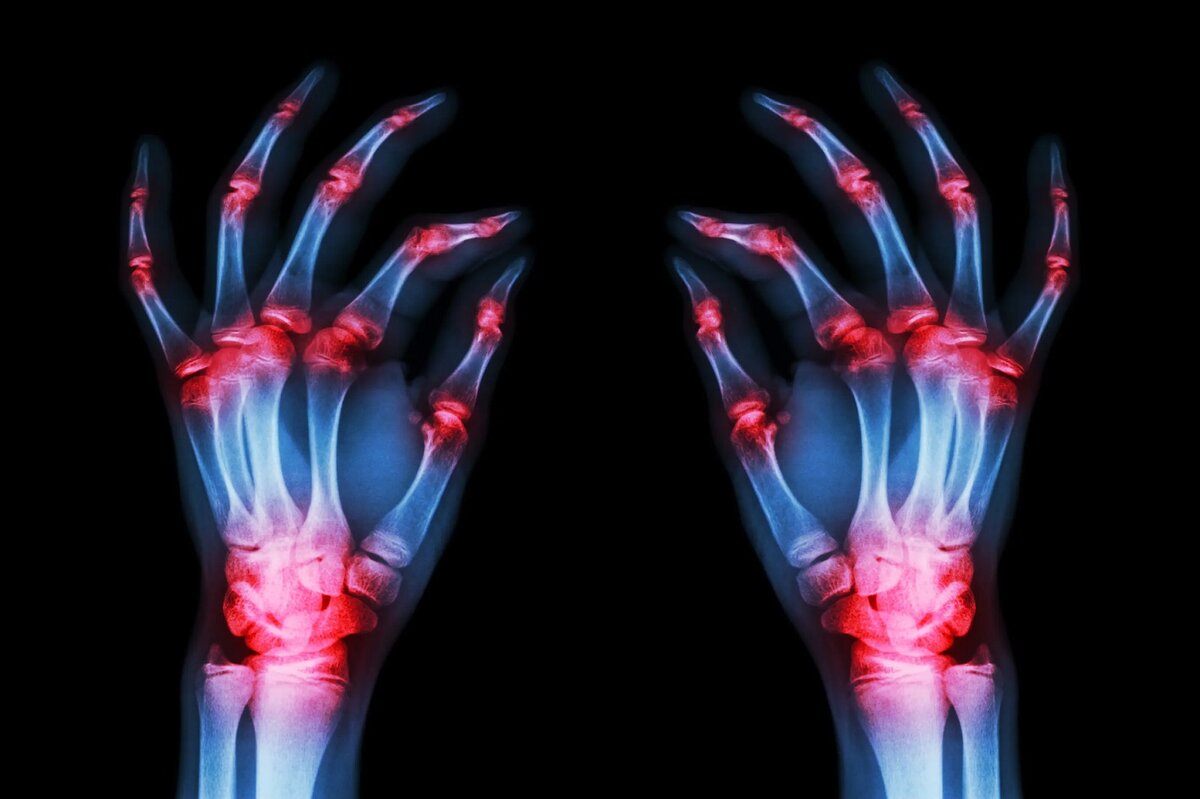

Ученые нашли способ блокировать воспаление, вызываемое ревматоидным артритом: открытие, которое перевернет медицину